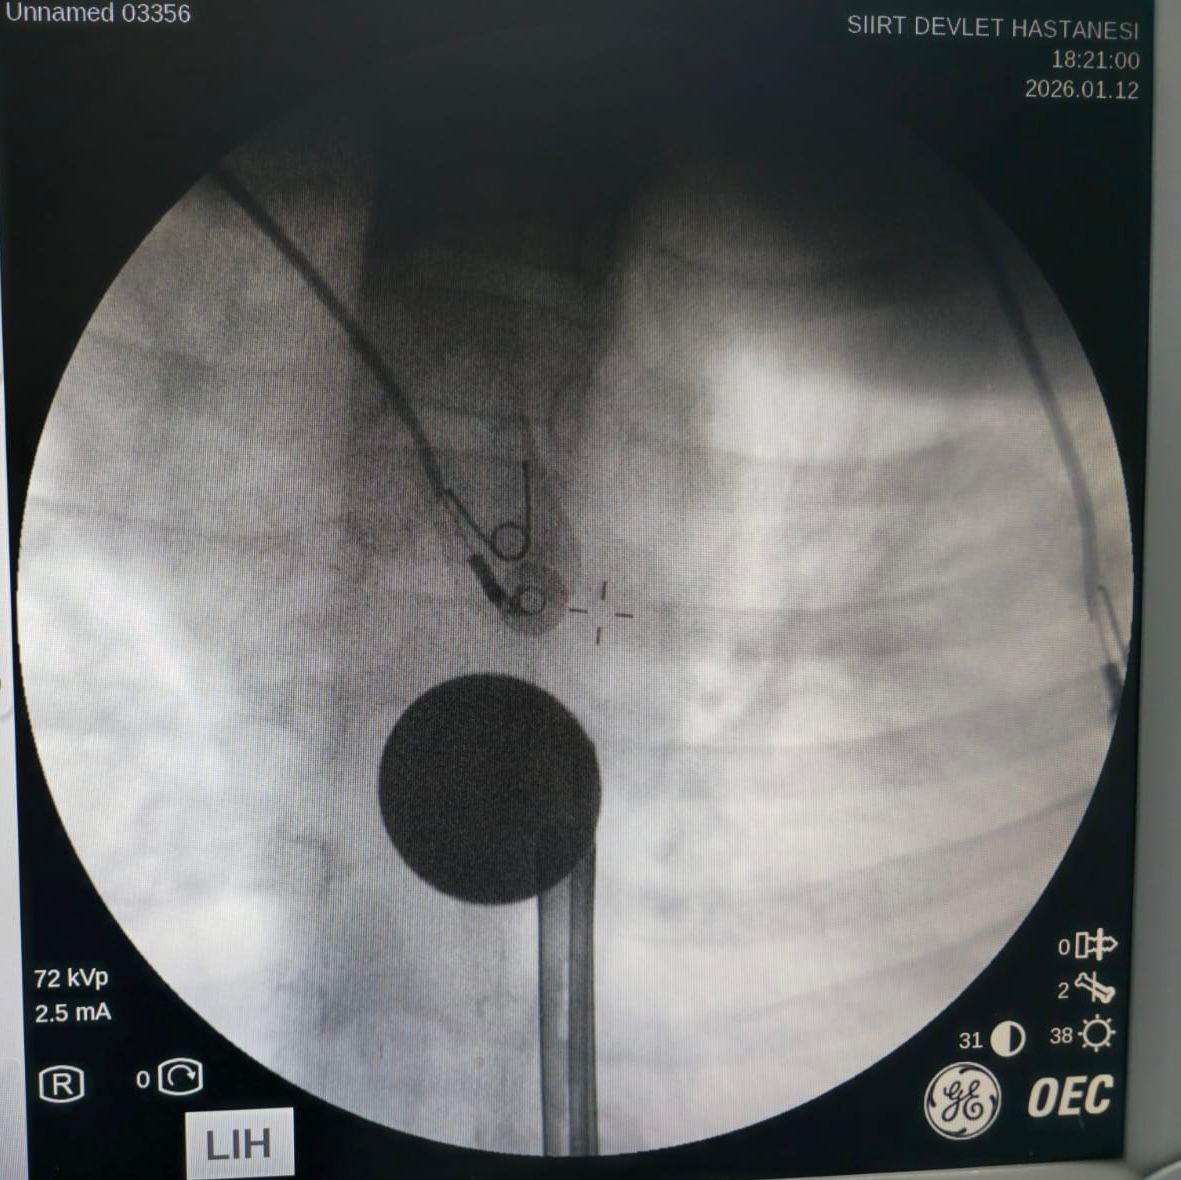

Siirt’te oyun oynadığı sırada boğazına cisim kaçan 8 yaşındaki Y.K., ailesi tarafından panikle Siirt Eğitim ve Araştırma Hastanesi’ne getirildi. Acil serviste yapılan ilk muayene ve çekilen görüntüleme tetkikleri sonucunda, küçük çocuğun madeni para yuttuğu ve paranın yemek borusunda takılı kaldığı tespit edildi.

Doktorların titiz müdahalesi sonucu, Y.K.'nın yemek borusuna kadar ilerleyen madeni 5 lira, cerrahi bir komplikasyon yaşanmadan başarıyla çıkarıldı. Operasyonun ardından bir süre müşahede altında tutulan küçük çocuk, genel sağlık durumunun iyi olması üzerine taburcu edildi.